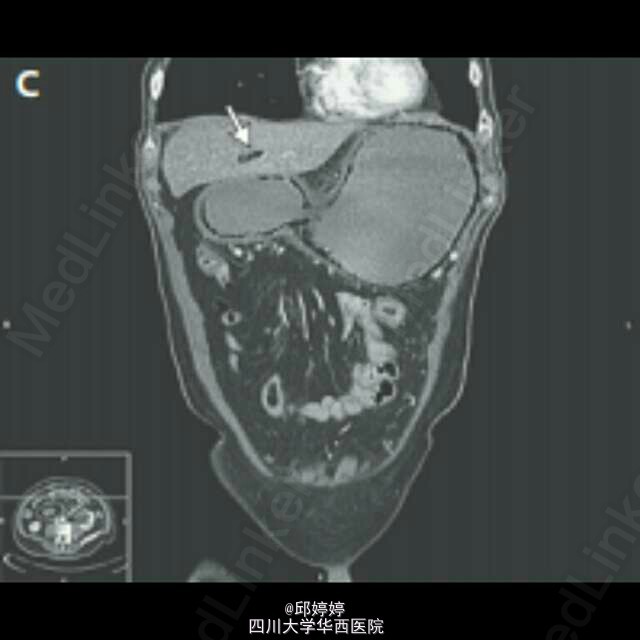

灾难性胃肠积气

患者,老年男性,胰腺癌晚期,腹痛,呕吐12h,触诊腹部压痛,板状腹。平片(图1)示腹腔严重积气,CT(图2-3)示胃肠周围,门静脉积气。患者拒绝治疗,48h后死亡。